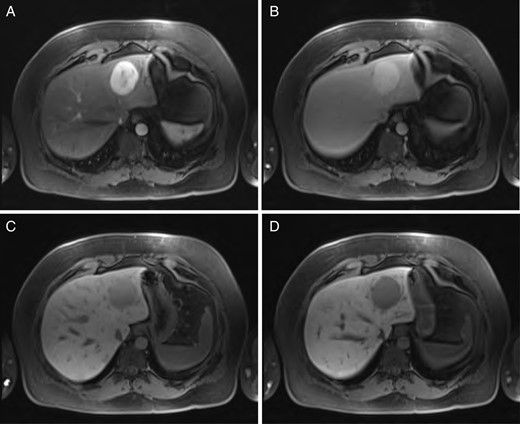

Sequential MRI imaging of hepatic hemangioma. Note delayed centripetal filling: (A) T1 arterial phase, (B) T1 60-s delay phase, (C) T1 postcontrast phase and (D) T1 hepatographic phase.

Hepatic hemangioma is a common hepatic incidentaloma that has characteristic features on both CT and MRI. Triple-phase imaging will reveal a hypoattenuating lesion on the early phase, while the delayed phases show peripheral isoattenuation (with the rest of the liver parenchyma) with a persistently hypoattenuating central portion that gradually fills [6]. This is due to the centripetally oriented vascular drainage of the lesion, flowing from the periphery toward the center.